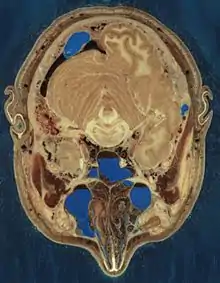

The Visible Human Project is an effort to create a detailed data set of cross-sectional photographs of the human body, in order to facilitate anatomy visualization applications. It is used as a tool for the progression of medical findings, in which these findings link anatomy to its audiences.[1] A male and a female cadaver were cut into thin slices, which were then photographed and digitized. The project is run by the U.S. National Library of Medicine (NLM) under the direction of Michael J. Ackerman. Planning began in 1986;[2] the data set of the male was completed in November 1994 and the one of the female in November 1995. The project can be viewed today at the NLM in Bethesda, Maryland.[3] There are currently efforts to repeat this project with higher resolution images but only with parts of the body instead of a cadaver.

The male cadaver was encased and frozen in a gelatin and water mixture in order to stabilize the specimen for cutting. The specimen was then "cut" in the axial plane at 1-millimeter intervals. Each of the resulting 1,871 "slices" was photographed in both analog and digital, yielding 15 gigabytes of data. In 2000, the photos were rescanned at a higher resolution, yielding more than 65 gigabytes. The female cadaver was cut into slices at 0.33-millimeter intervals, resulting in some 40 gigabytes of data.

The data are supplemented by axial sections of the whole body obtained by computed tomography, axial sections of the head and neck obtained by magnetic resonance imaging (MRI), and coronal sections of the rest of the body also obtained by MRI.